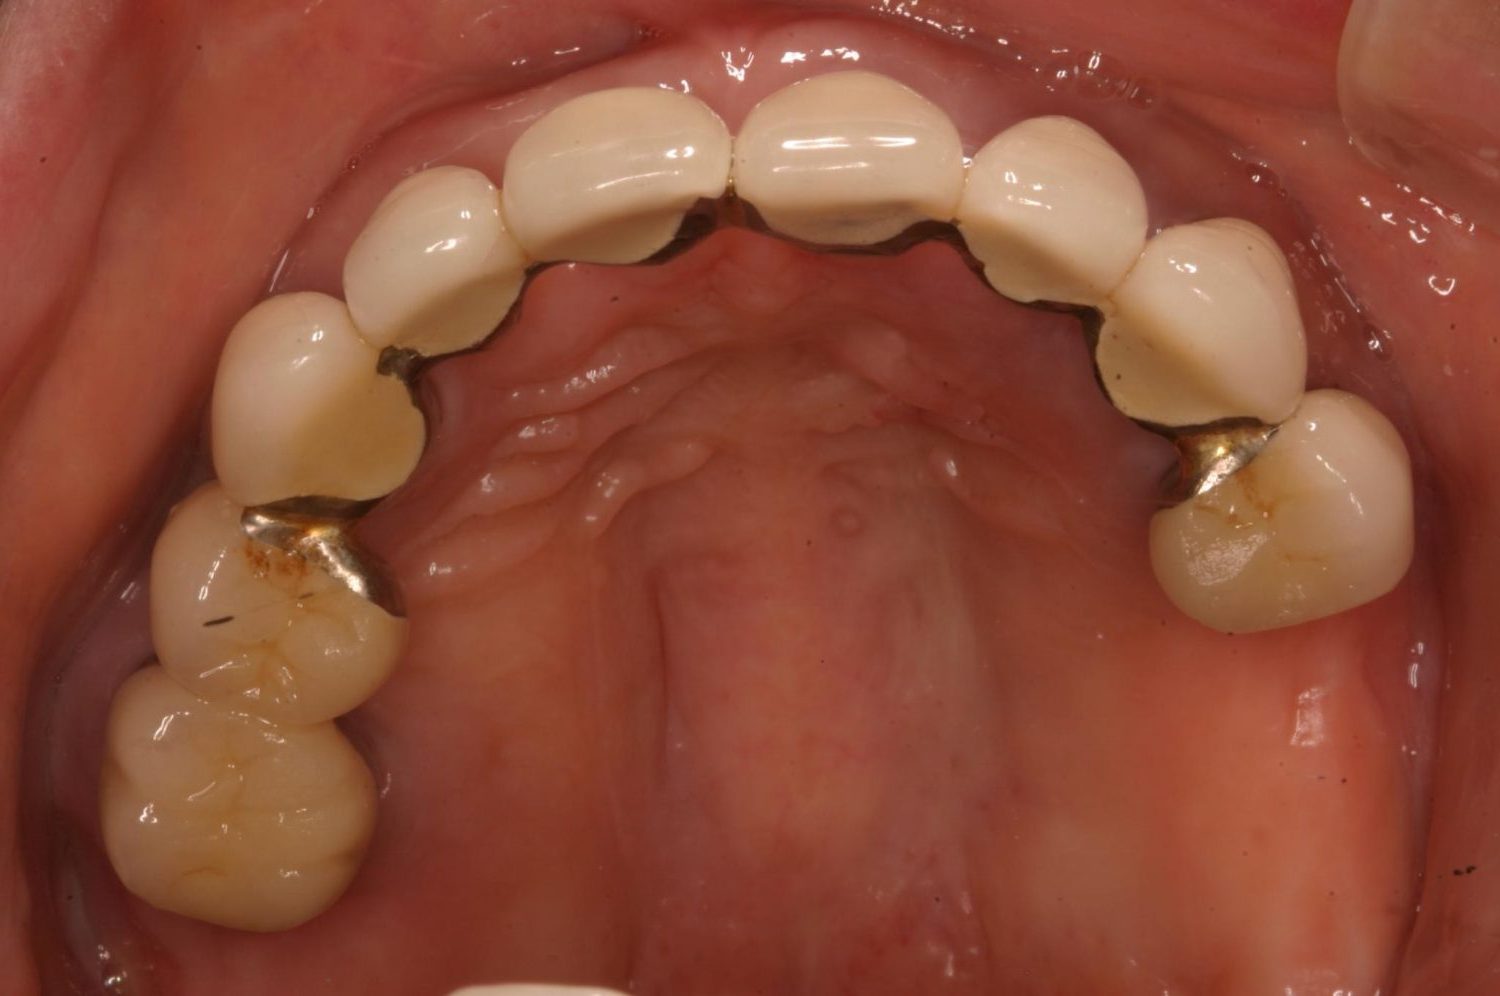

インプラント治療の症例紹介③

Before

After

主訴

むし歯の治療

治療内容

保存不可能な歯の抜歯

下顎にインプラント埋入し咬合再構成

治療費

2,688,400円(税込)

治療期間

14か月

治療回数

21回

想定されたリスク

※上部構造の形態が複雑になるため清掃が難しくなる。インプラント周囲炎の恐れがありました。

濱 仁隆先生

浜歯科

多数歯う蝕および多数歯欠損による咬合崩壊、保存不可能な歯の抜歯により上下無歯顎に。下顎に6本インプラント埋入する事で咬合再構成を行った。